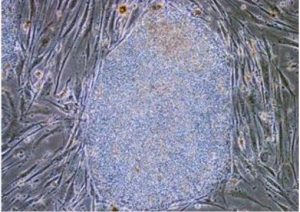

![]() 중국과학원 상하이 Pasteur연구소의 리빈(李斌) 연구진이 미국 Johns Hopkins대학의 연구진과 공동으로 생물화학과 분자면역학, 질병동물모델 등의 방법을 결합해 세균성 염증유발 성분인 지질다당체(lipopolysaccharide, LPS)와 염증전구물질(proinflammatory cytokines) 등의 위험신호에 의해 활성화되는 네거티브 조절 경로를 발견하고, 염증 조건에서 FOXP3+ 조절형 T세포의 면역억제기능이 상실되는 새로운 분자메커니즘을 규명하였다. 관련된 연구성과는 최근 《Immunity》지에 게재되었고, 2건의 국제특허를 출원하였다. FOXP3은 T세포의 면역억제 기능에 매우 중요하다. 과학자들이 일찍이 염증인자 신호가 T세포의 면역억제 기능을 상실시킨다는 사실을 발견했지만, 그 분자메커니즘에 대해서는 아직까지 규명하지 못하고 있다. 리빈(李斌) 연구진이 감염과 기타 염증 환경 속에서 발열, 지질다당체, 염증전구물질 등의 자극을 받으면, 인간 T세포가 유도발현 등의 경로를 통해 Ⅰ형 인터페론의 유도발현 및 면역반응의 활성화 등에 관계되는 효과유전자를 획득할 수 있음을 발견하였다. Johns Hopkins대학의 연구진은 장염 생쥐모델의 T세포를 이용해 인간 T세포 관련 상기 발견을 입증하였다. 이 연구성과는 염증환경 속 FOXP3+ 조절형 T세포의 기능 안정성과 그 조절과정을 심층적으로 이해하는데 중요한 의의가 있고, 감염성 질환, 자가면역성 질환, 과민성 질환, 종양과 기관이식 등에 새로운 약물타깃과 임상간섭 수단을 제공하였다는 높은 평가를 받았다. 정보출처 : http://news.sciencenet.cn/sbhtmlnews/2013/9/277478.shtm |